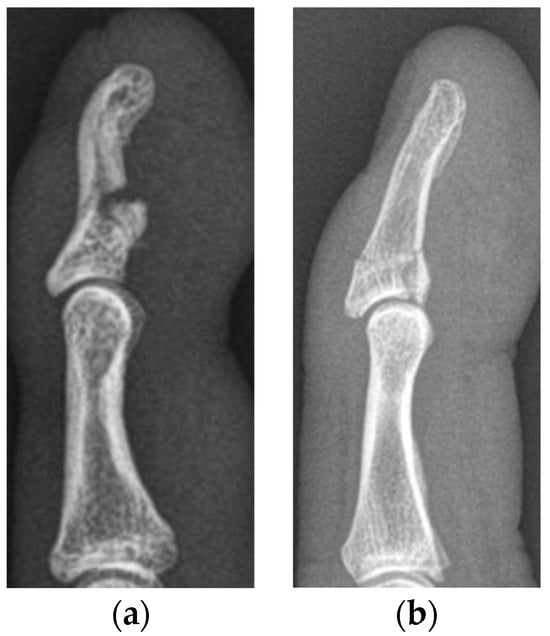

All medical records of the patients, including the discharge summaries, as well as diagnostic, therapeutic and operative reports, together with radiographic, CT and MR images, were included in the evaluation of the patients for this study. All images were analyzed using an IMPAX workstation (Agfa, Ridgefield Park, NJ, USA). Due to calibration of magnification and distances of performed medical imaging, exact distance measurements were facilitated. All patients were analyzed in the corresponding jersey finger subtype group. Furthermore, we subdivided the patient cohort into two subgroups: (1) severe displaced (SD), matching at least one indication for surgery as mentioned above, and (2) minimally displaced (MD) injuries (Figure 2).

Figure 2. Lateral radiographs of a minimally displaced type Va (a) and type Vb (b) jersey finger, treated conservatively in our department.